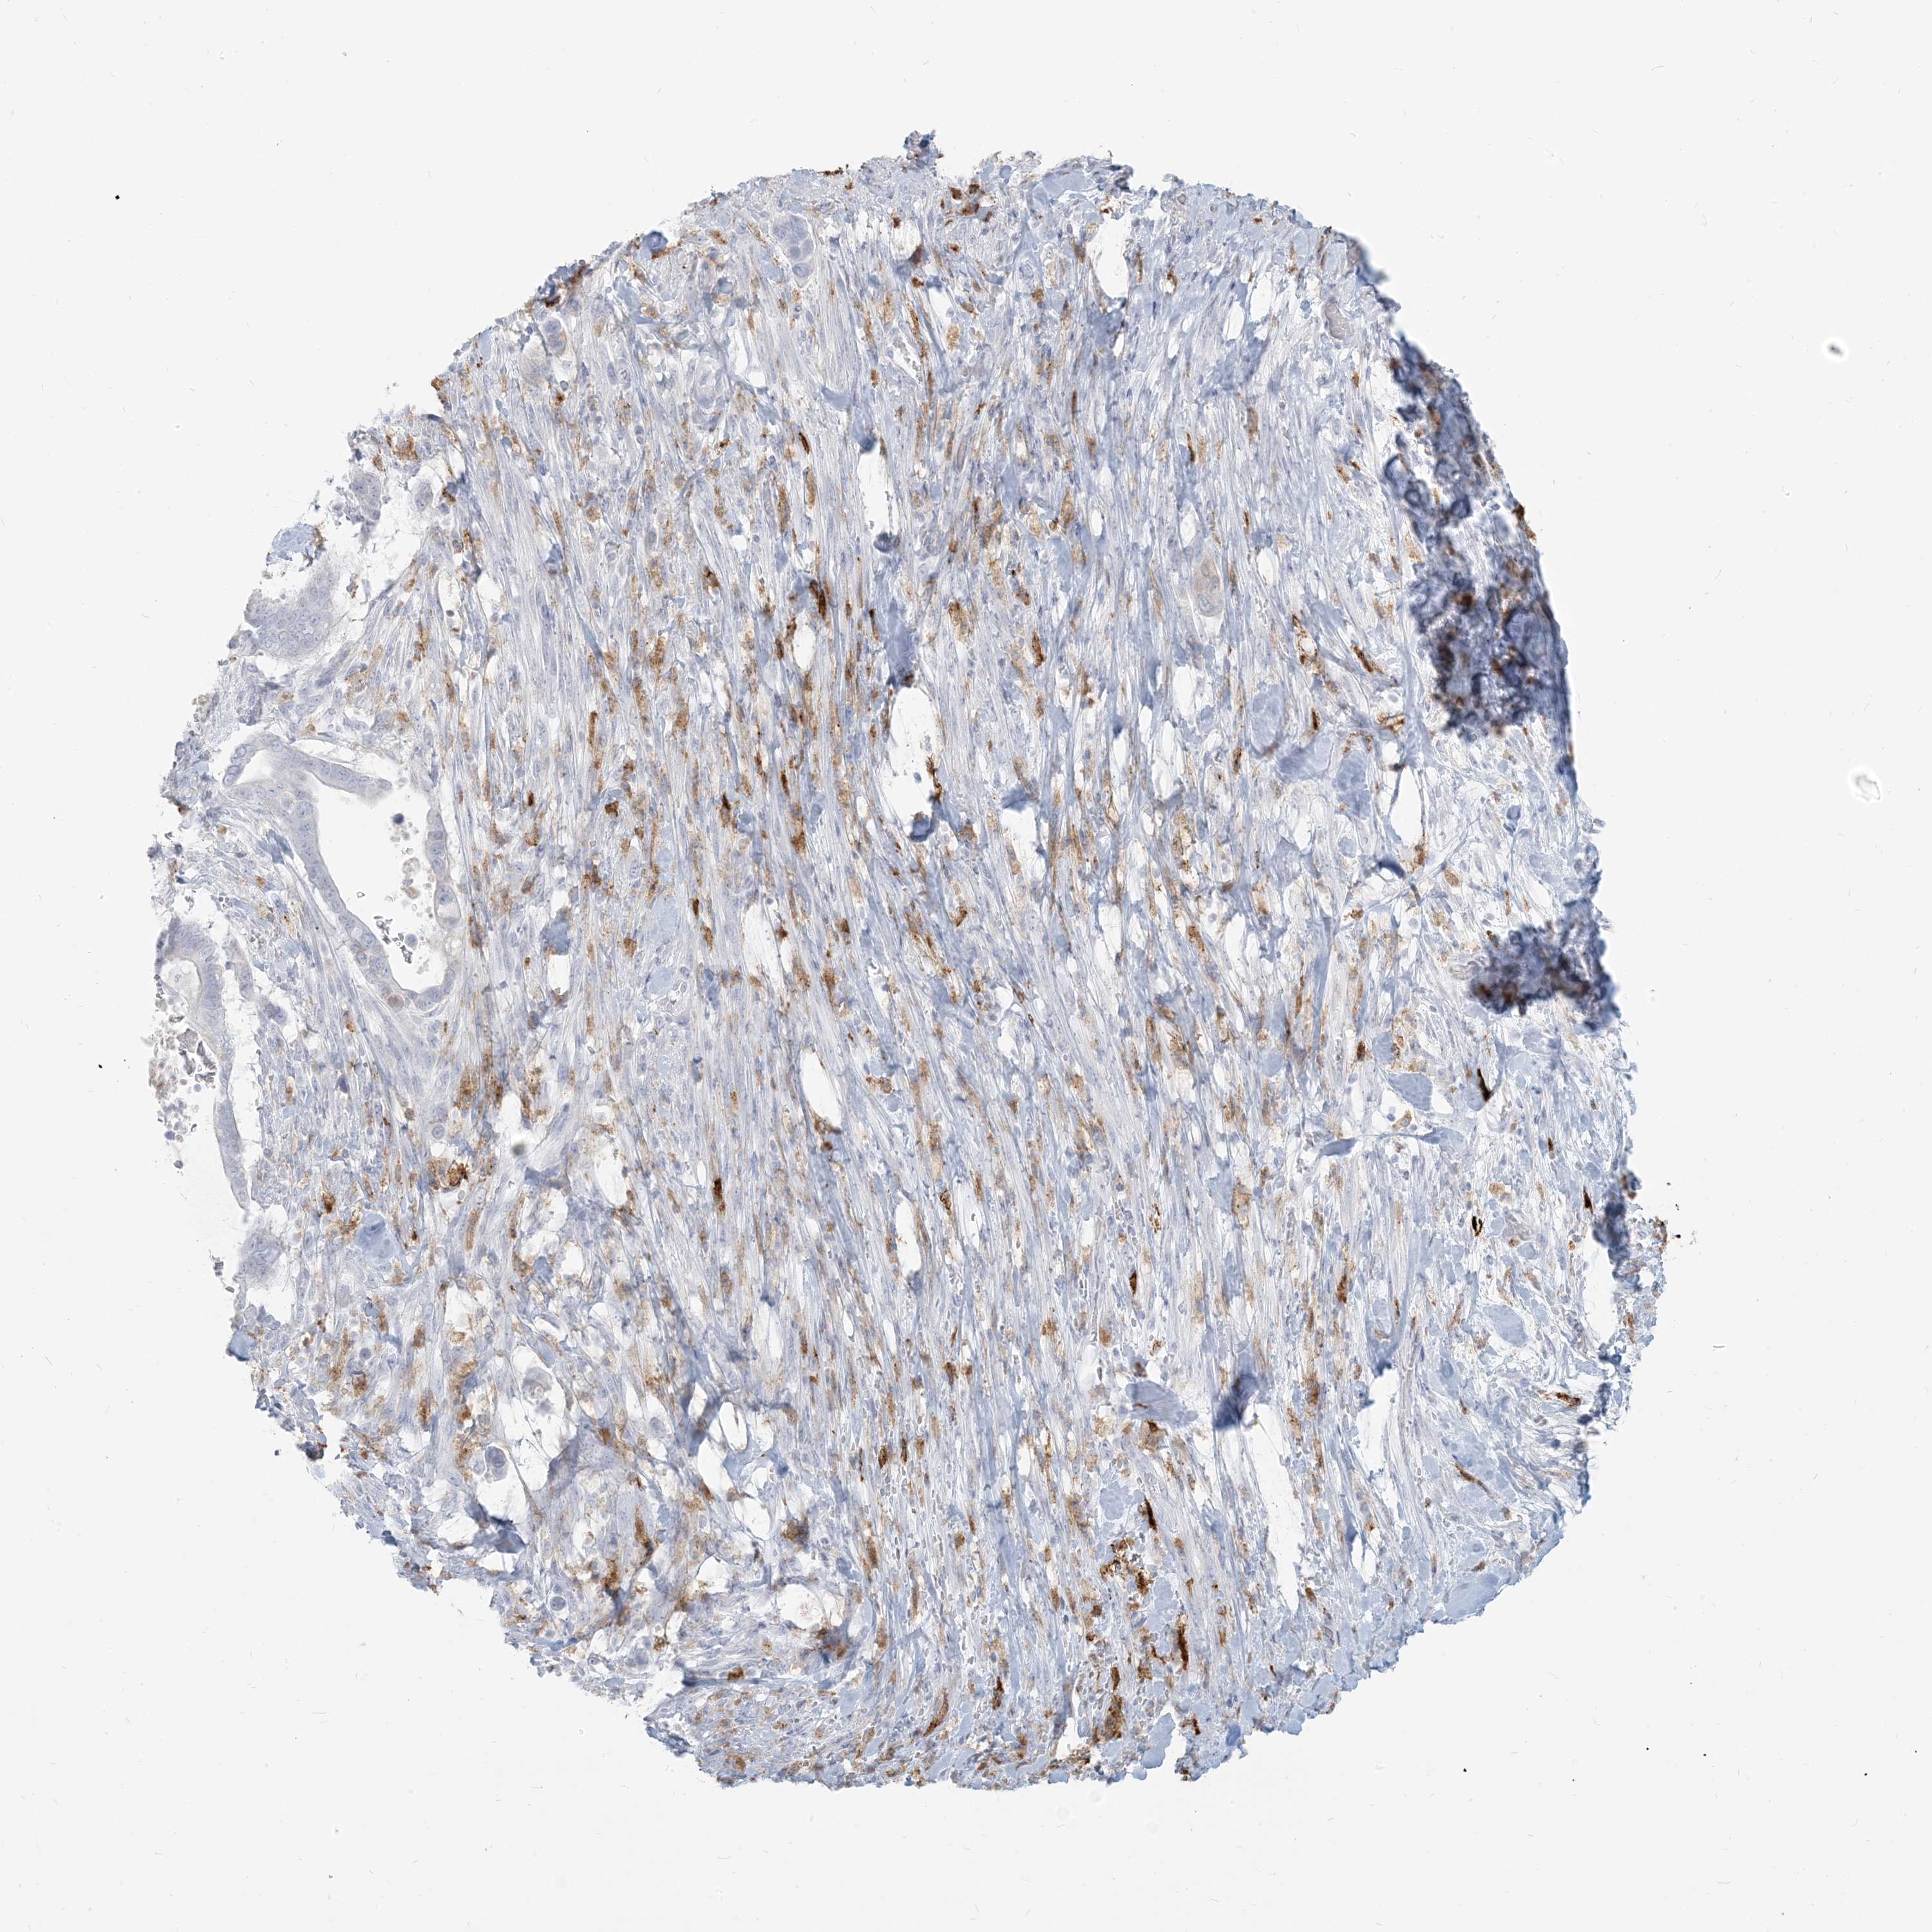

PANCREATIC CANCER - Protein expressioni

A mouse-over function shows sample information and annotation data. Click on an image to view it in a full screen mode. Samples can be filtered based on level of antibody staining by selecting one or several of the following categories: high, medium, low and not detected. The assay and annotation is described here.

Note that samples used for immunohistochemistry by the Human Protein Atlas do not correspond to samples in the TCGA dataset.

Antibody stainingi

Antibody staining in the annotated cell types in the current human tissue is reported as not detected, low, medium, or high, based on conventional immunohistochemistry profiling in selected tissues. This score is based on the combination of the staining intensity and fraction of stained cells.

Each image is clickable and will lead to virtual microscopy that enables deeper exploration of all samples and also displays staining intensity scores, fraction scores and subcellular localization as well as patient and tissue information for each sample.

Antibody HPA043151

Antibody CAB015400

Antibody CAB034021

Staining

High

Medium

Low

Not detected

Intensity

Strong

Moderate

Weak

Negative

Quantity

>75%

75%-25%

<25%

None

Location

Nuclear

Cytoplasmic/membranous

Cytoplasmic/membranous,nuclear

Adenocarcinoma, NOS